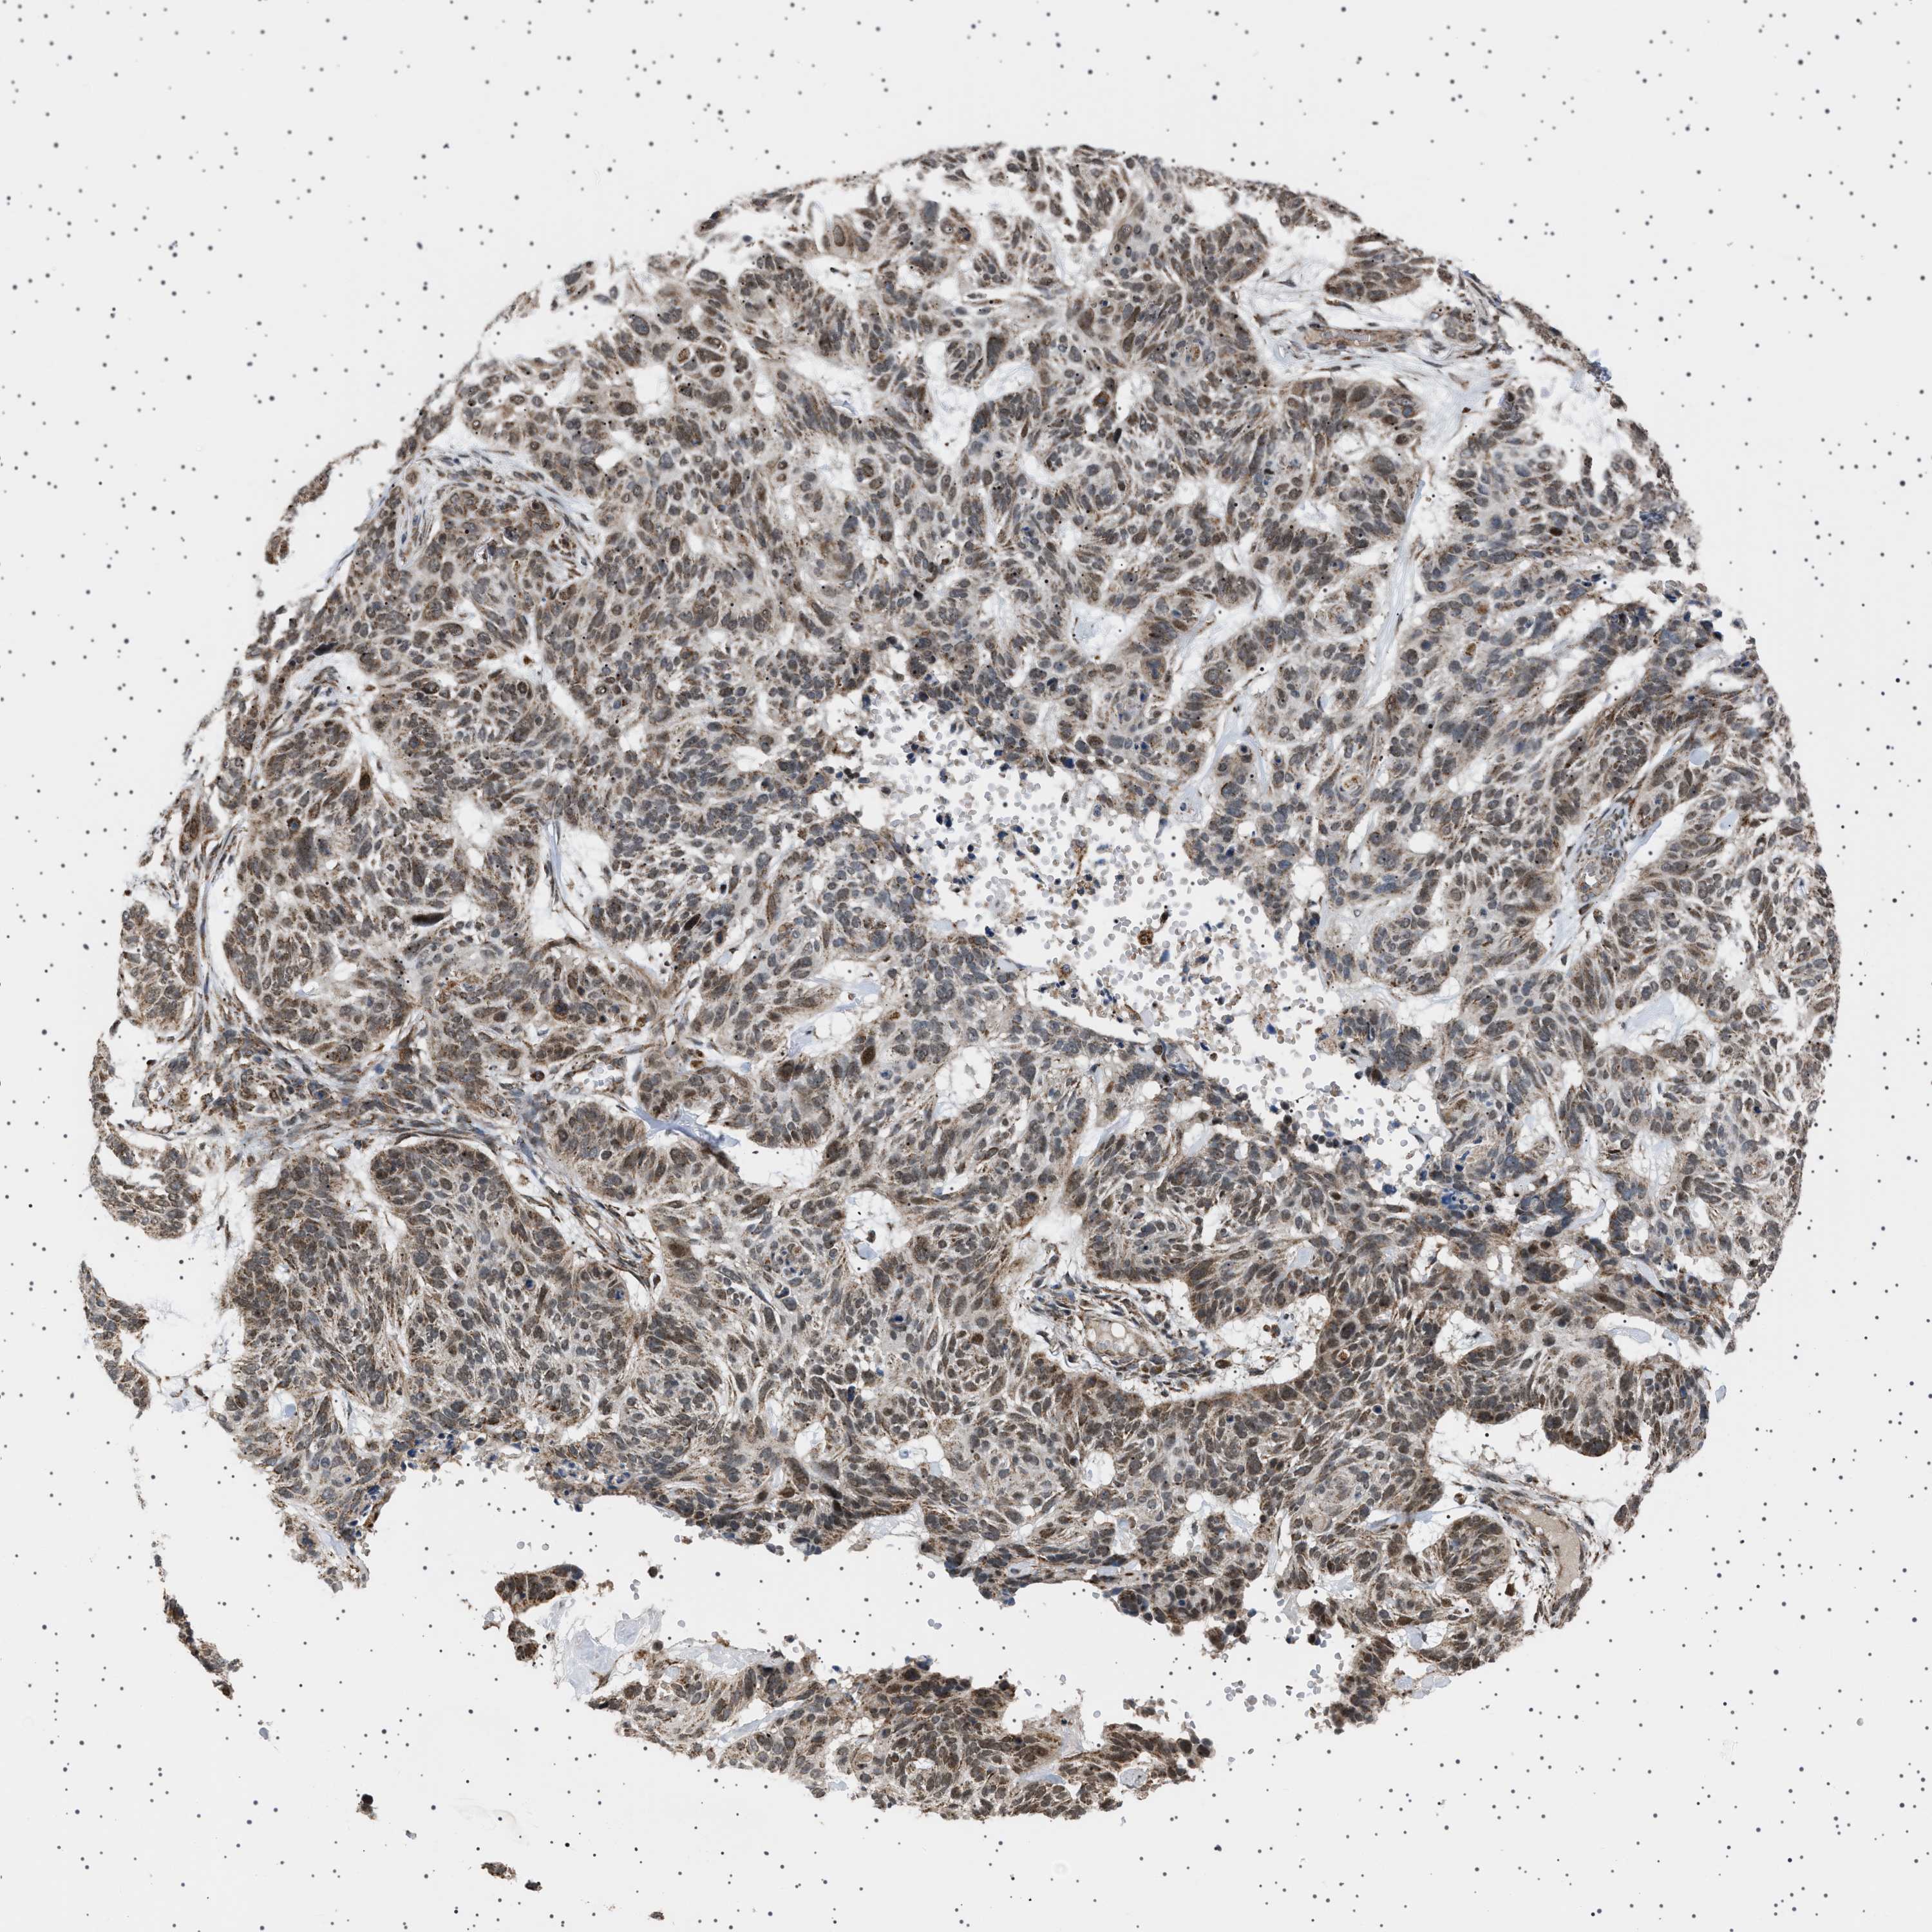

SKIN CANCER - Protein expressioni

A mouse-over function shows sample information and annotation data. Click on an image to view it in a full screen mode. Samples can be filtered based on level of antibody staining by selecting one or several of the following categories: high, medium, low and not detected. The assay and annotation is described here.

Antibody stainingi

Antibody staining in the annotated cell types in the current human tissue is reported as not detected, low, medium, or high, based on conventional immunohistochemistry profiling in selected tissues. This score is based on the combination of the staining intensity and fraction of stained cells.

Each image is clickable and will lead to virtual microscopy that enables deeper exploration of all samples and also displays staining intensity scores, fraction scores and subcellular localization as well as patient and tissue information for each sample.

Antibody HPA017214

Staining

High

Medium

Low

Not detected

Intensity

Strong

Moderate

Weak

Negative

Quantity

>75%

75%-25%

<25%

None

Location

Nuclear

Cytoplasmic/membranous

Cytoplasmic/membranous,nuclear

Squamous cell carcinoma in situ, NOS

Squamous cell carcinoma, NOS